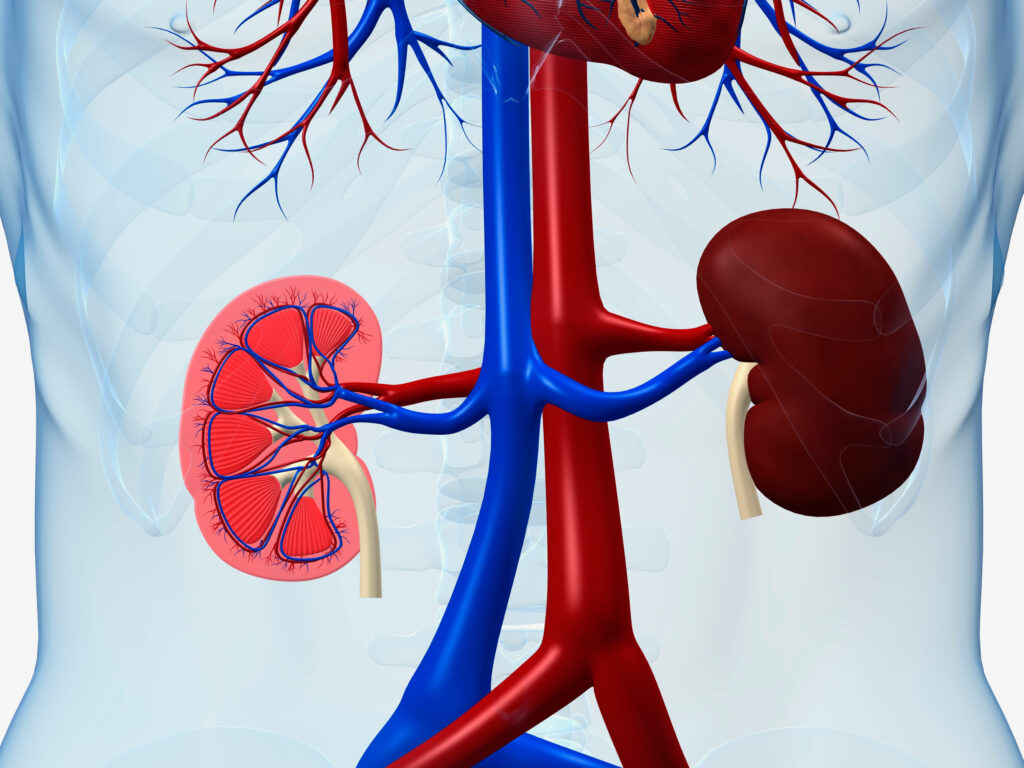

Diseases of the kidney rank among the top 10 causes of death in the United States. It has a higher mortality rate than either breast or prostate cancer. Kidney disease can be detected in its early stages, when there are no symptoms, with just a few simple blood and urine tests.

Modifications to a healthy lifestyle are the primary therapy. The kidney is responsible for maintaining proper fluid balance as well as regulating the production of red platelets.

A glomerulus, which is essentially a tiny vein, links each nephron to a tubule of the kidney. Some instances include glioma, polycystic kidney disease, kidney stones, and urinary tract infections (UTIs). Donating a kidney is possible for anyone who is in good health.